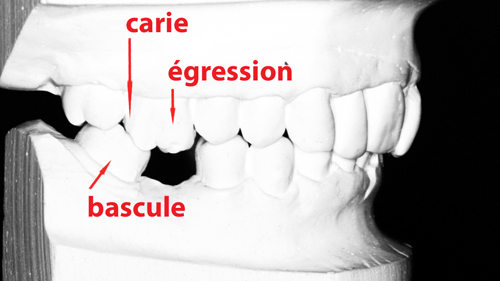

La perte d’une dent peut avoir des conséquences importantes sur les dents adjacentes. En effet, ces dernières peuvent basculer et se déplacer, entraînant des caries et des problèmes de gencives. Pour éviter cela, il est recommandé de remplacer la dent manquante par un bridge ou une couronne sur implant afin de stabiliser les dents et de prévenir les mouvements dentaires indésirables.

Si une dent manque et que les dents adjacentes se sont penchées, ou, situation fréquente, si plusieurs d’entre elles sont manquantes en arrière, alors la mâchoire du bas n’est plus correctement calée, et l’articulation du côté concerné est comprimée. Les conséquences peuvent être multiples : douleurs, bourdonnements, craquements ou claquements du ménisque articulaire, contractures musculaires.